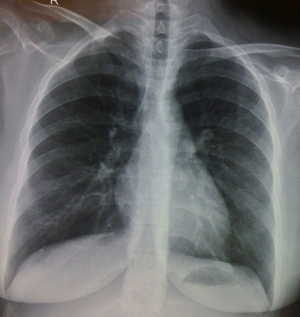

Empyema thoracis (Figures 2,3) can be a complication of pneumonia, tuberculosis or various iatrogenic pulmonary interventions. Despite widespread use of highly effective antibiotics, chronic empyema thoracis (CET) is common worldwide. Corrective procedures like tube thoracostomy, image directed catheters, thoracoscopic drainage, decortication and open drainage have all been employed with success rates varying between 10% to 90% (12). VATS has shown promising results in decortication and adhesiolysis. Perioperative bleeding and air leak are the main concerns in extensive adhesiolysis and decortication. Modern electronic chest drainage systems with suction capability are a boon as it gives the estimate of air leak, drain, helps in lung expansion and early mobility. Talc pleurodesis is employed in an effort to prevent recurrence in patients with repeated effusions.